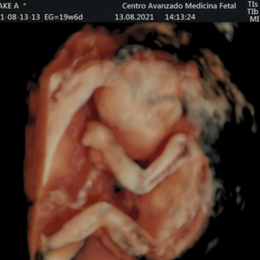

Ecografía del corazón fetal en 4D

Ocho de cada mil bebes nace con algún defecto cardíaco congénito. Estas anomalías se producen por un desarrollo anormal del corazón durante el embarazo y pueden consistir en defectos de sus paredes o válvulas, o de los vasos sanguíneos que entran o salen de él.